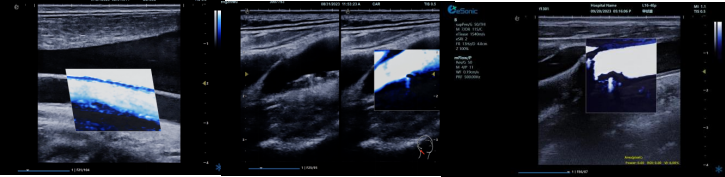

image.png

? 运用 3D 壁滤波技术智能分析信号,可探测常规超声难以捕捉的低速血流,灵敏度高。

? 依据 Staub 标准对检查结果分级,直观展示斑块内新生血管血流,为斑块稳定性评估提供新指标。

? 基于多普勒原理,进行频谱测量并可进行VI指数测量,定量评估斑块内新生血管占比。

? 相较超声造影成像,无创便捷,为颈动脉易损斑块评估开辟新途径。